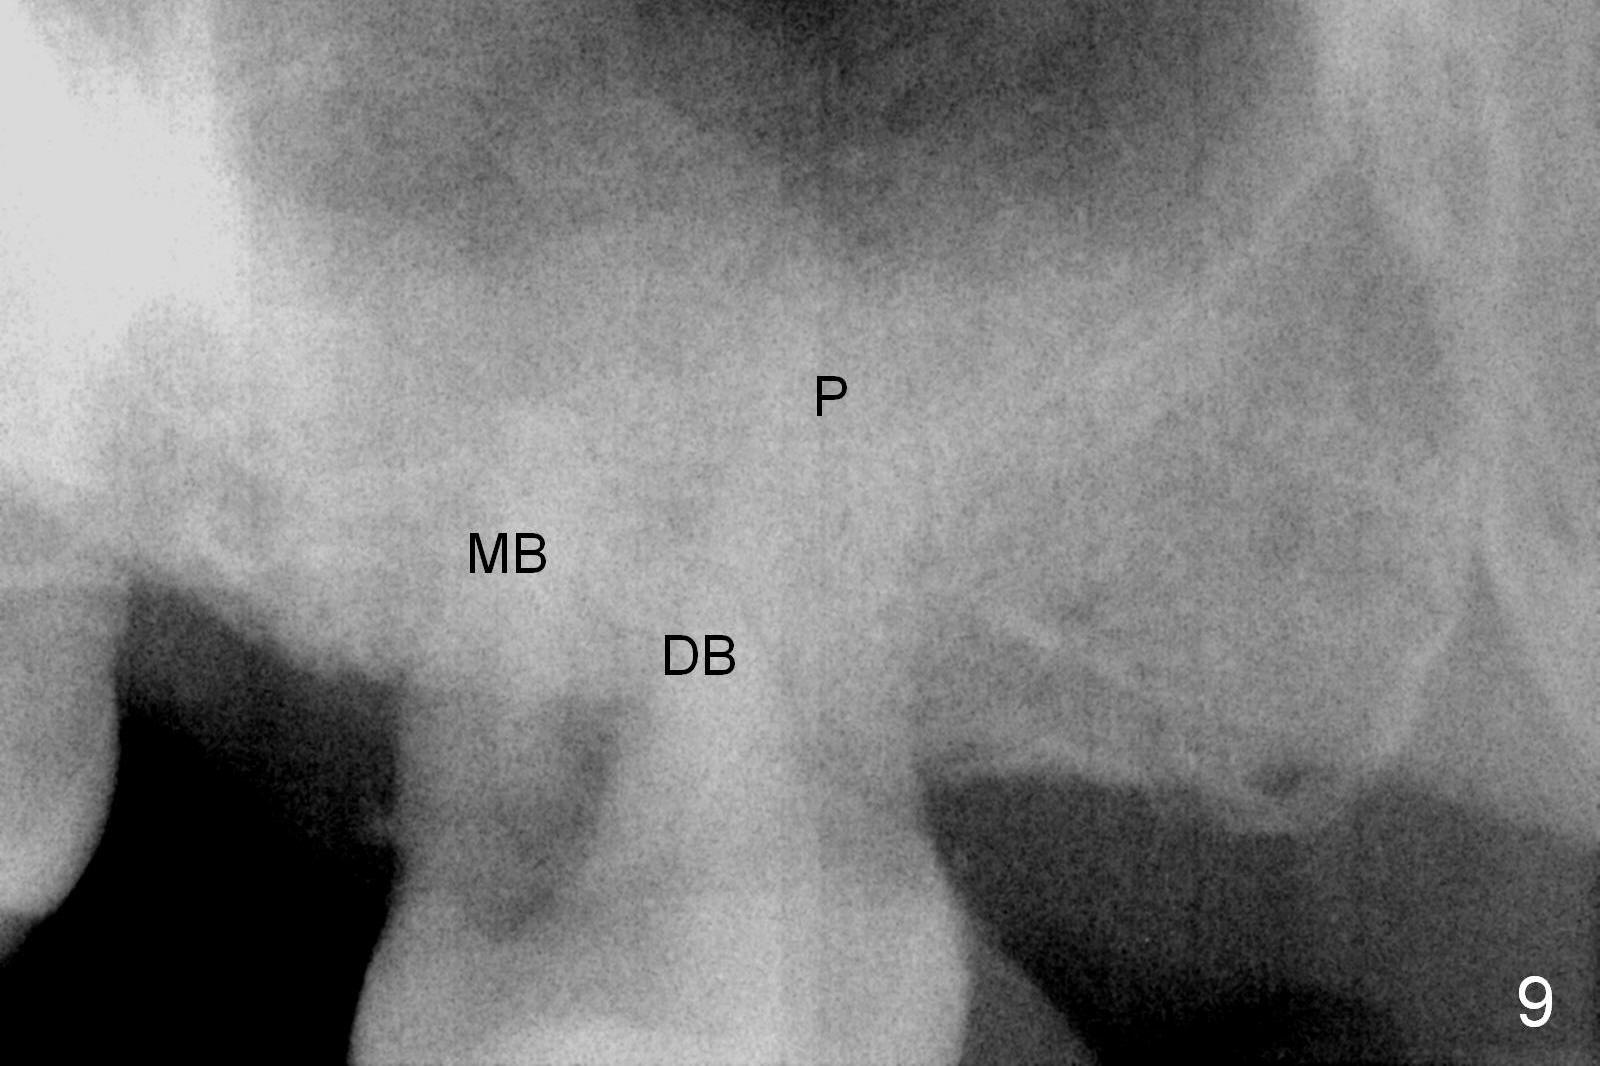

By comparing the root morphology of an extracted tooth (Fig.7,8: #15) with that of X-ray (Fig.9) repeatedly, we can develop an ability to visualize the septum prior to surgery.